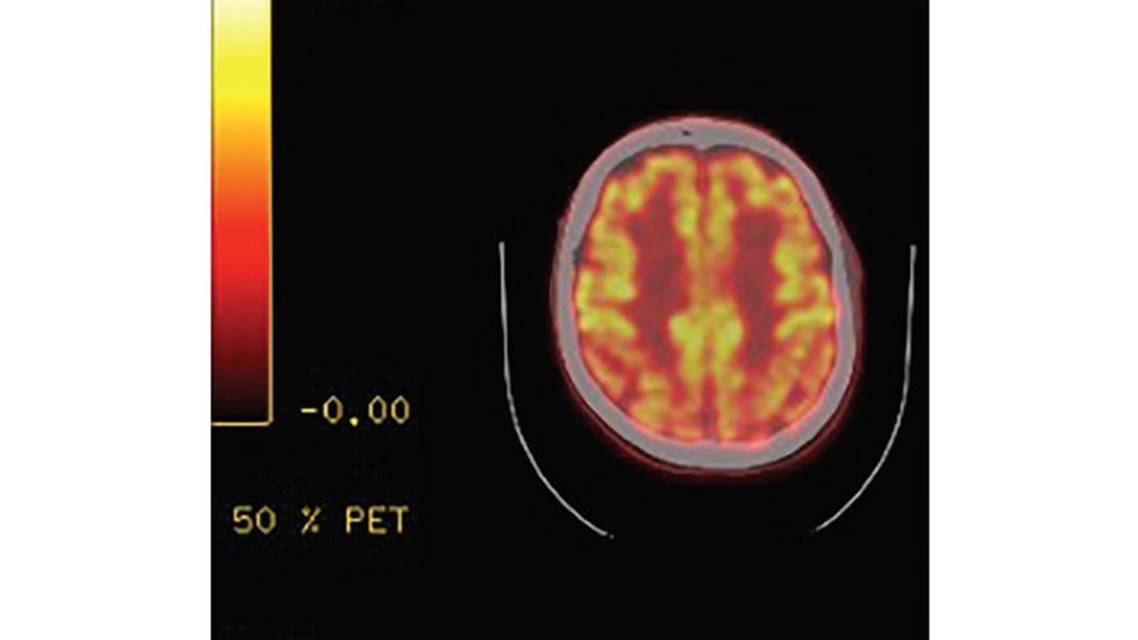

At this point, 4 years after the acute encephalitis, Mr. E had a positron emission tomography (PET) scan that showed reduced posterior activity (Figure). He had developed mild bilateral upper extremity rigidity in addition to his shuffling gait. His voice had progressively become increasingly hypophonic. At a 6-year follow up visit, Mr. E had developed some mild bilateral bradykinesia and postural instability with a backwards tug test. His face had become more masked. Treatment with carbidopa-levodopa was begun with minimal effect. Mr. E and his family, however, chose to continue with carbidopa-levodopa because they felt it helped with Mr. E’s anxiety. He continued taking rivastigmine at 15 mg/day, which had been titrated above the recommended daily dose on his family’s own initiative because of the profound and positive effect of rivastigmine on Mr. E’s visual hallucinations. Day-to-day fluctuations, day-time sleepiness, and parkinsonism continued to progress over time.

Mr. E has documented cognitive deficits on neuropsychologic testing with cognitive changes beginning during his acute VZV encephalitis. The constellation of visual hallucinations, REM-behavior disorder, day-to-day fluctuations, parkinsonism, and a PET scan with reduced posterior cortical metabolism are suggestive of Lewy body dementia (LBD). His response to rivastigmine was quite dramatic and unexpected. However, these deficits remained stable over a 3-year period without the expected progression of a true dementia.

We have considered whether Mr. E’s viral encephalitis unmasked a predisposition to LBD or if and infectious brain injury may have caused a clinical syndrome similar to LBD. The visual hallucinations, progressive parkinsonism, REM-behavior disorder, day-to-day fluctuations, and reduced posterior activity on PET scan are all suggestive of LBD. However, in contrast to typical findings of LBD, Mr. E’s neuropsychologic test results are relatively stable. His age at presentation is less typical for LBD as well. In addition, none of the symptoms discussed were present his acute viral illness. Although there is no definitive test to confirm the diagnosis, the time over which Mr. E has been followed and the overall progression in symptoms are helpful in determining his diagnosis.